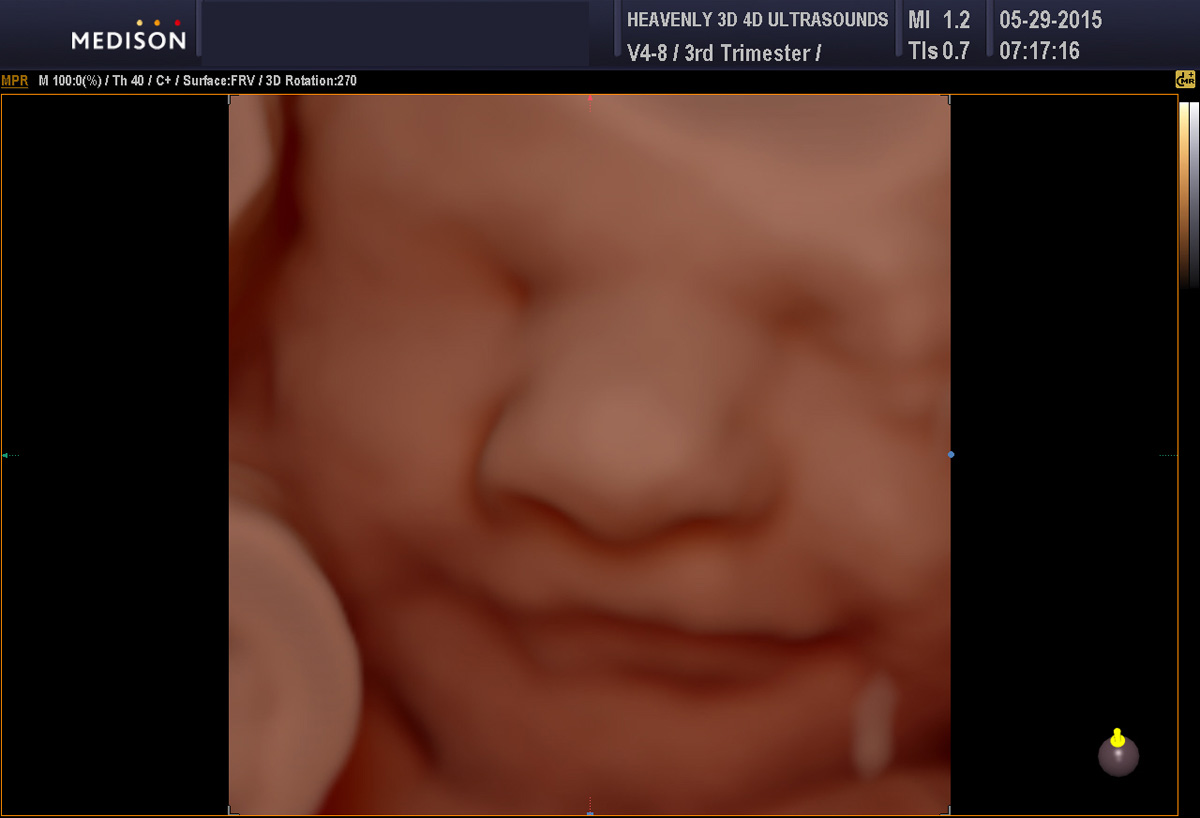

Heavenly 3d 4d Ultrasound Near Me

Heavenly 3d 4d has 4 office locations including fontana apple valley upland and baldwin park heavenly 3d 4d ultrasound baby 3d ultrasound 4d ultrasound in apple valley and upland ca skip to content.

199 reviews of heavenly 3d 4d ultrasounds heavenly 3d 4d ultrasounds is located across the street from walmart directly across from the entrance to walmart where the wells fargo sign is. She knew i was disappointed and worked really hard to find our baby s gender. Parking is located in the back entrance will be from the elevator. Using the latest in 3d 4d fetal imaging prenatal peek allows you to view your baby during a relaxed personalized and unique 3d 4d ultrasound session.